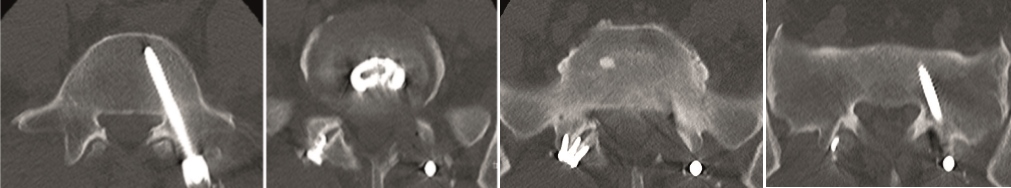

A less invasive approach was used with Insight Retractor using the bilateral Facet Wedge. No bone graft. X-ray follow-up after 3 months and CT assessment after 6 months (Fig 18-19).

A conventional approach for posterior correction was taken, with indirect Foraminal decompression and Facet Wedge fusion (apex curve). Facet Wedge introduction after curve correction with rod in situ. X-ray follow-up initially (Fig 20), with CT assessment of Facet Wedge fusion after 6 months (Fig 21).